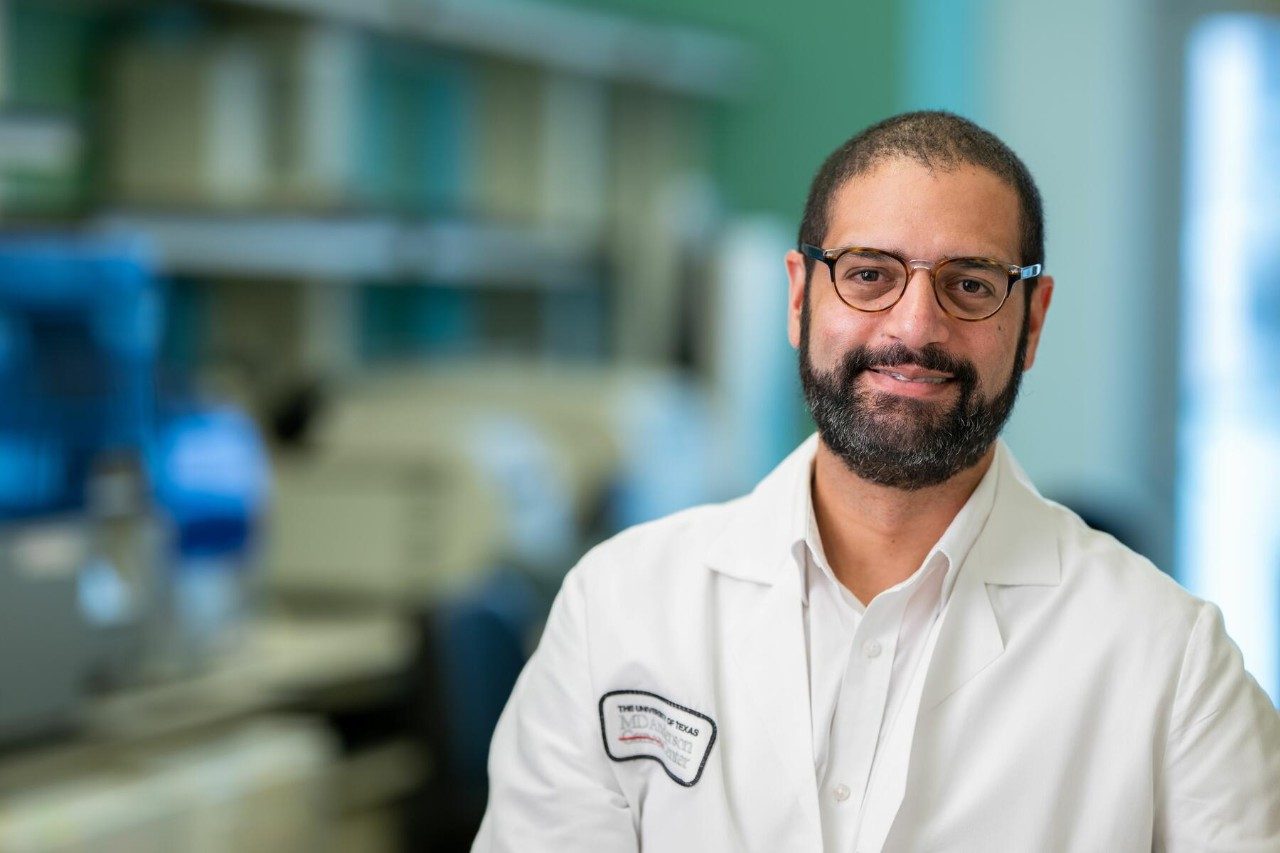

4. Targeted combination with evorpacept for patients with B cell non-Hodgkin lymphoma

Paolo Strati, M.D., associate professor of Lymphoma and Myeloma, had led a Phase I study of evorpacept (a novel high-affinity signal regulatory protein that blocks CD47), with lenalidomide and rituximab (R2) in patients with relapsed or refractory indolent B cell non-Hodgkin lymphoma. The combination was safe, and more than 80% of patients had a complete response.

Strati is now presenting a Phase II study investigating the efficacy of this regimen in patients with previously untreated indolent B cell non-Hodgkin lymphoma and a high tumor burden. These included patients with both follicular lymphoma and marginal zone lymphoma.

The results indicated that adding evorpacept to R2 is safe and effective as a frontline non-chemotherapy treatment for indolent B cell non-Hodgkin lymphoma. In the study, 92% of patients experienced a complete response, and 8% had a partial response, for an overall response rate of 100%. With limited follow-up, responses seem durable. The researchers are currently evaluating serial blood samples for circulating tumor DNA to determine the minimal residual disease eradication rate with this novel regimen.